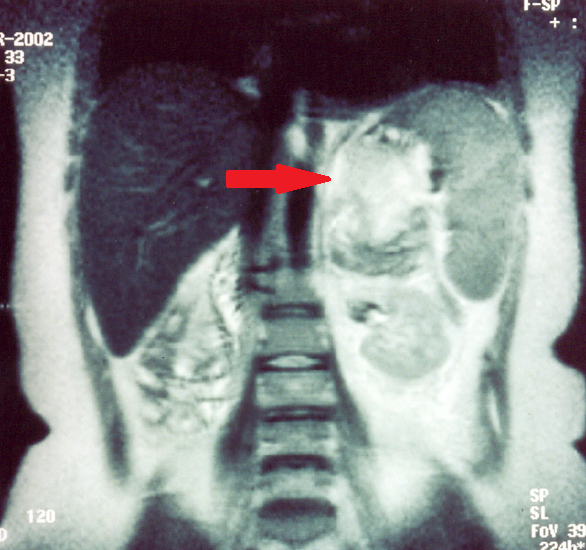

Neck CT. Red arrow — Large cyst on the right, compressing the esophagus, with well-defined margins and colloid content (Courtesy Dr. V. Penopoulos)